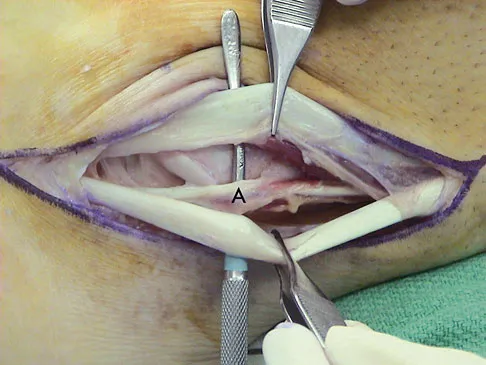

A 35-year-old man is seen for evaluation of his left ankle following multiple previous ankle sprains and frequent episodes of the ankle giving way. Examination reveals marked laxity about the lateral ankle with associated tenderness along the peroneal tendons. Physical therapy, anti-inflammatory drugs, and supportive bracing have failed to provide relief. An MRI scan shows peroneal tenosynovitis and a possible tear. He elects to undergo a peroneal tendon repair and lateral ligament reconstruction. Which of the following best describes the structure labeled "A" in Figure 45?

Explanation